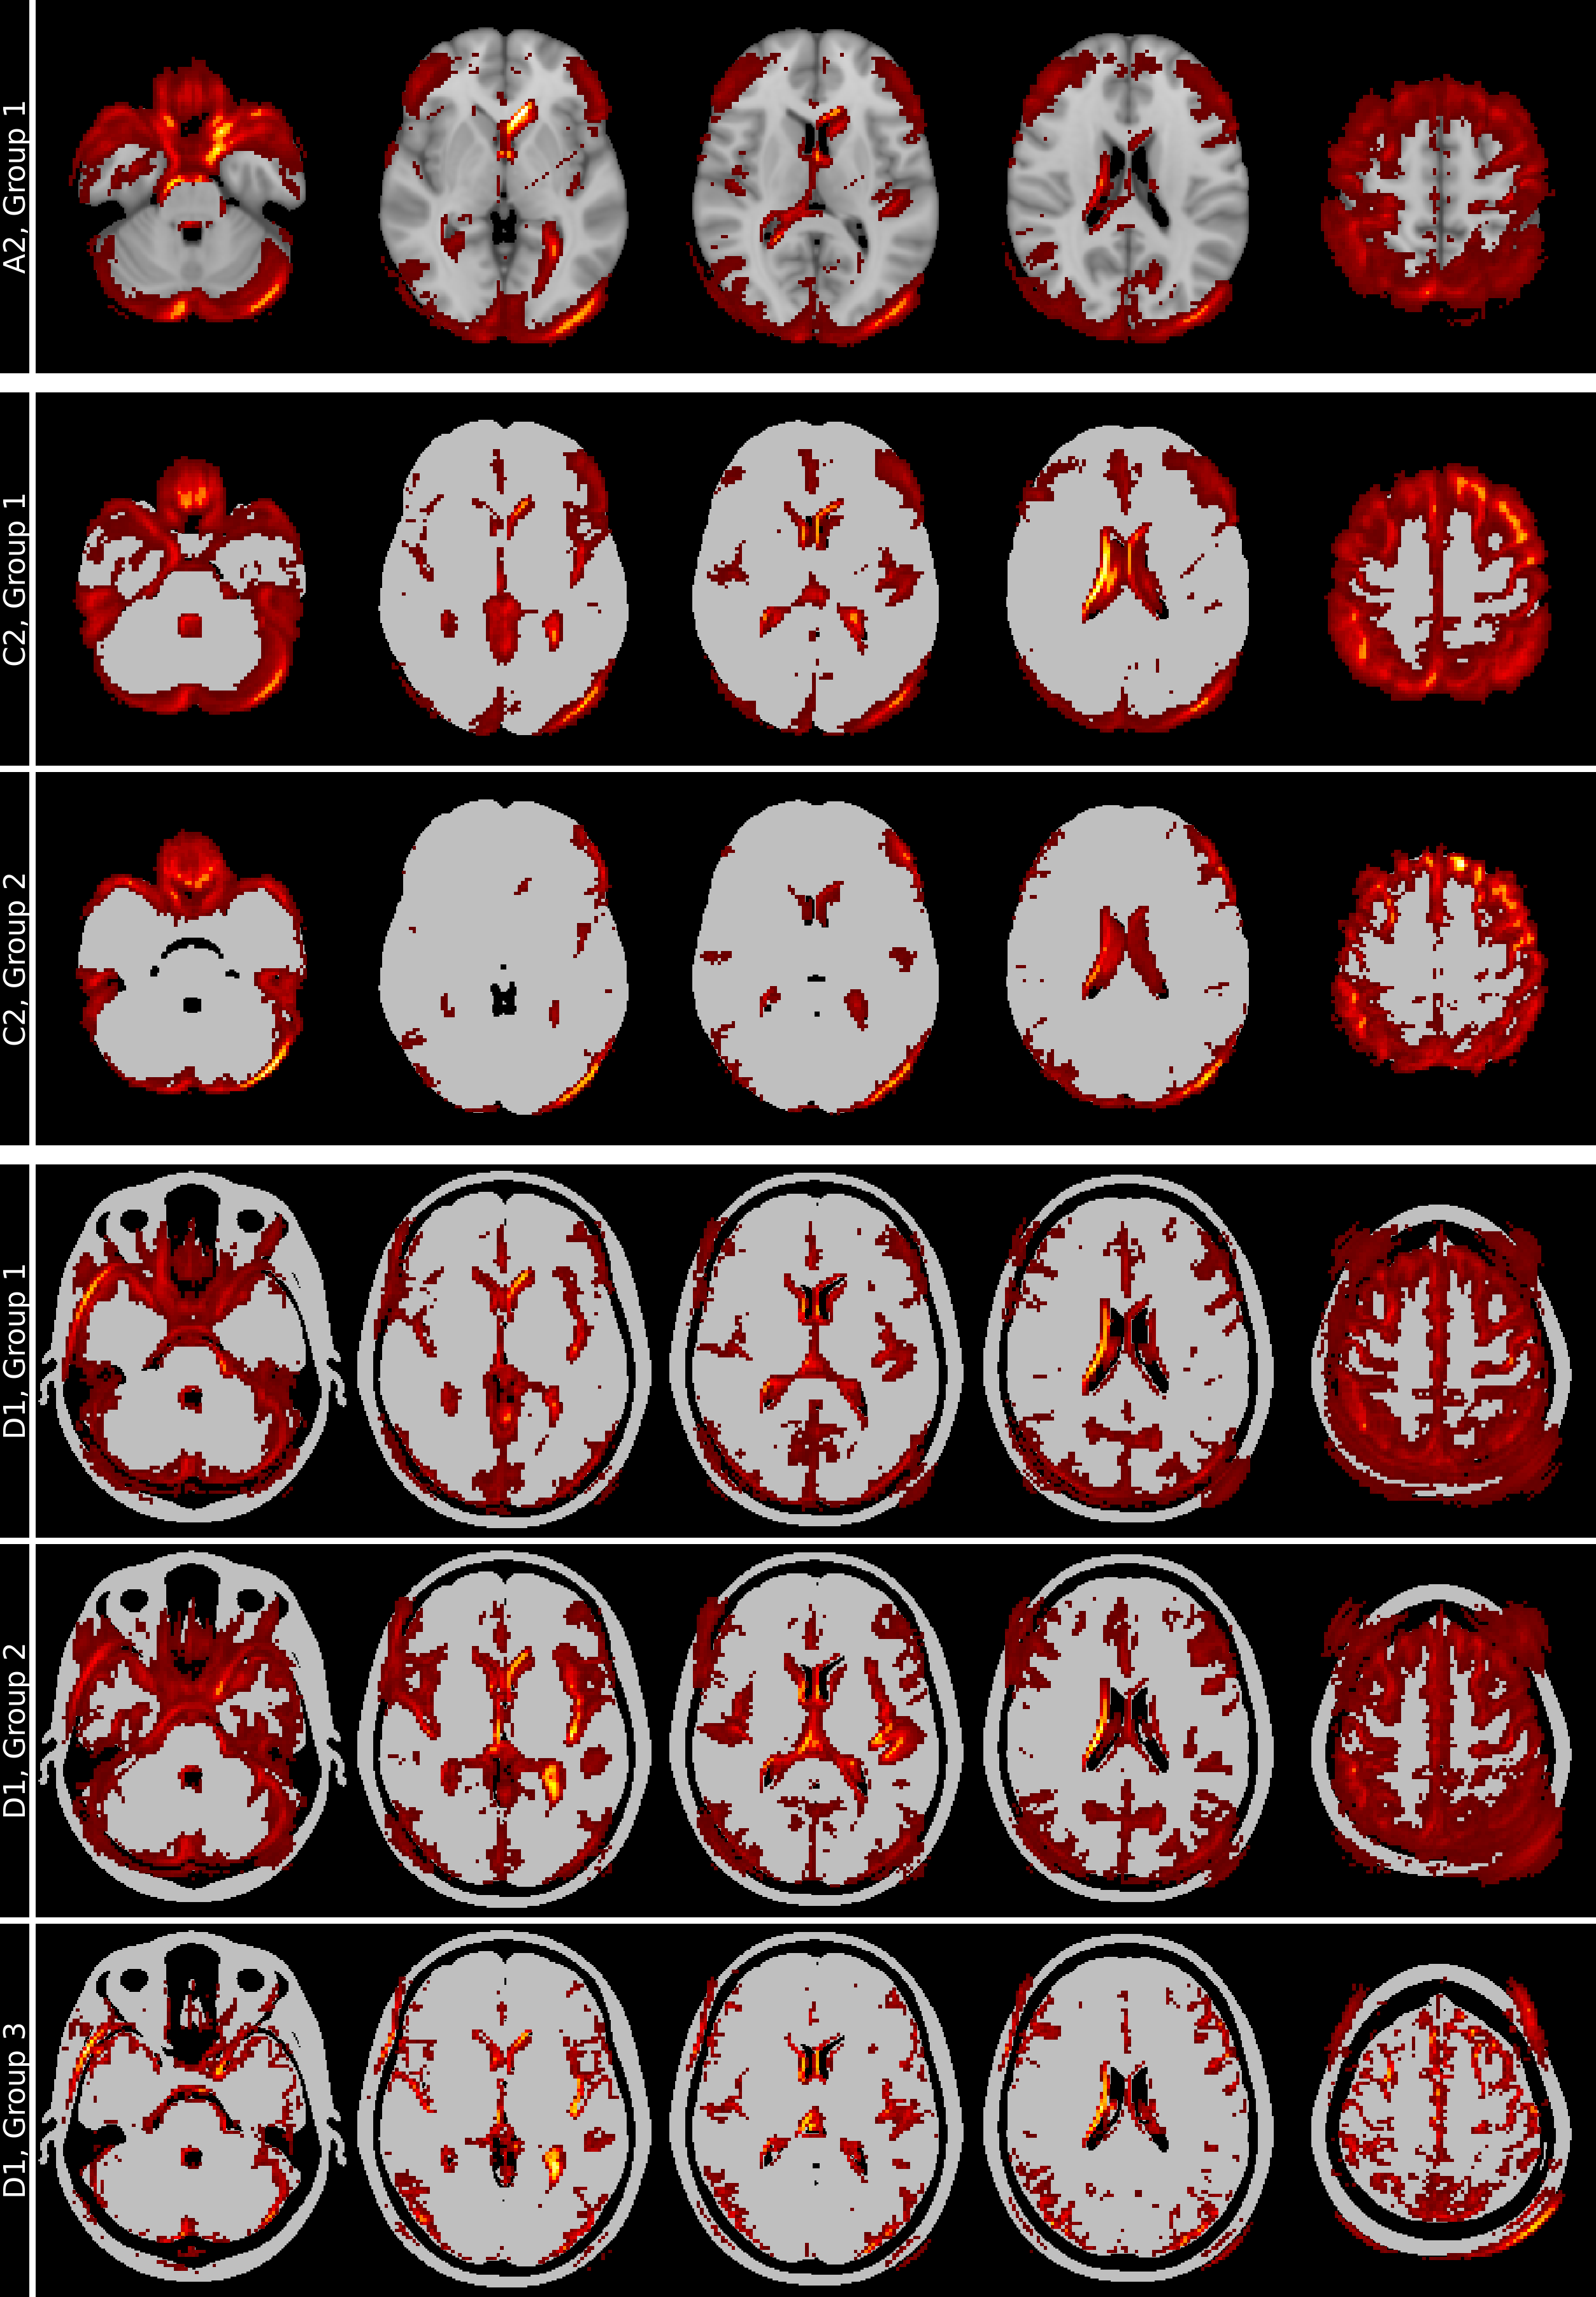

Results of spectral relevance analysis

We visualized the clustering of inputs and heatmaps using t-SNE, initialized with the normalized, symmetric, and positive semi-definite Laplacian matrix derived from the spectral clustering affinity matrix. Figure 9 illustrates the grouping of inputs and corresponding heatmaps for the reference model (skull-stripped, no binarization, A2), the 27.5% binarized skull-stripped model (C2), and the 41.25% binarized model without skull-stripping (D1). Group mean heatmaps, based on spectral clustering groupings, are presented in Figure 10.

The analysis of the eigenvalues and the eigenvalue gaps of the Laplacians and the t-SNE visualization of input and heatmap groupings for all eight models are given in Figures 11,  12,  13, and  14. Additionally, Figures 15 and  16 present the analysis of misclassified samples and the corresponding heatmaps for models A2 and C2 using SpRAy.

Discussion of spectral relevance analysis

The t-SNE visualization of input images and corresponding heatmaps in Figure 9 demonstrated that only the 41.25% binarized model without skull-stripping (D1) exhibited a heatmap grouping aligned with the underlying subject groups (NC vs. AD) while having similar classification performance as the reference model (A2). This suggests that models trained on highly preprocessed images, such as skull-stripped or lower-threshold binarized data, may introduce additional biases that alter feature utilization. The observed eigenvalue gaps (see Figures  11,  12,  13, and  14) further confirmed the presence of distinct classifier behaviors, with spectral clustering successfully distinguishing dominant and atypical relevance patterns.

The mean heatmaps in Figure 10, derived from heatmap spectral clustering groupings, highlight consistent relevance patterns, offering insight into the classifier’s decision strategies. In model D1 (41.25% binarization without skull-stripping), the separation between AD (Group 2) and NC (Group 1) predictions is more pronounced than in models A2 (reference) and C2 (27.5% binarization with skull-stripping). The Group 2 mean heatmap in model D1 shows distinct relevance in the left insular cortex, suggesting a more structured and positionally distinct relevance pattern, consistent with the clustering observed in the t-SNE visualization. Group 3, while similar to Group 2, also highlights regions in the skull, which is an unexpected decision strategy for classifying AD.

Similar patterns are found for the misclassification analysis in Figures 15 and  16.

Refer to caption

Figure 9: t-SNE visualization of inputs (row 1) and heatmaps (row 2) for the reference model (A2), the 27.5% binarization model (C2), and the 41.25% binarization model without skull-stripping (D1). Input data points are labeled by group (NC or AD), while heatmap points are categorized by confusion matrix outcomes (TN, FN, TP, FP). Only the heatmaps of model D1 exhibit clustering that aligns with the subject groups (NC vs. AD). Note. NC: normal control; AD: Alzheimer’s disease; TN: true negative; FN: false negative; TP: true positive; FP: false positive.

Figure 10: Mean heatmaps for the groups identified using the individual heatmaps and spectral clustering for models A2, C2, and D1. Model D1 (41.25% binarization without skull-stripping) shows a clearer separation between AD (Group 2) and NC (Group 1) than A2 and C2. Group 2 in D1 highlights the left insular cortex, suggesting a more structured relevance pattern. Group 3, similar to Group 2, also shows relevance in the skull, indicating an unexpected decision strategy for AD classification. Images are shown in standard-radiological view, causing the left and right side of the brain to be flipped.